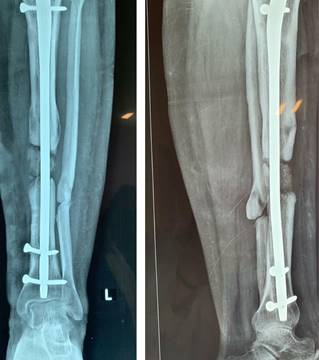

A las cuatro semanas posteriores se realiza el seguimiento sin datos de complicaciones postquirúrgicas, con cita a tal efecto en cuatro semanas con radiografía AP y lateral de pierna, en donde se observa una conveniente colocación de injerto, se realizan citas de verificación cada dos meses con radiografías de control; a los seis meses se perciben datos de consolidación acorde a la técnica, integrando puentes óseos en al menos tres corticales y exhibiendo marcha sin dolor (Figura 4), por lo que se inicia marcha asistida con bota larga tipo walker que deriva tolerada, la cual se retira a los dos meses.

Figura 4: Radiografía seis meses posteriores al inicio del tratamiento con técnica de Masquelet, con datos de consolidación ósea.